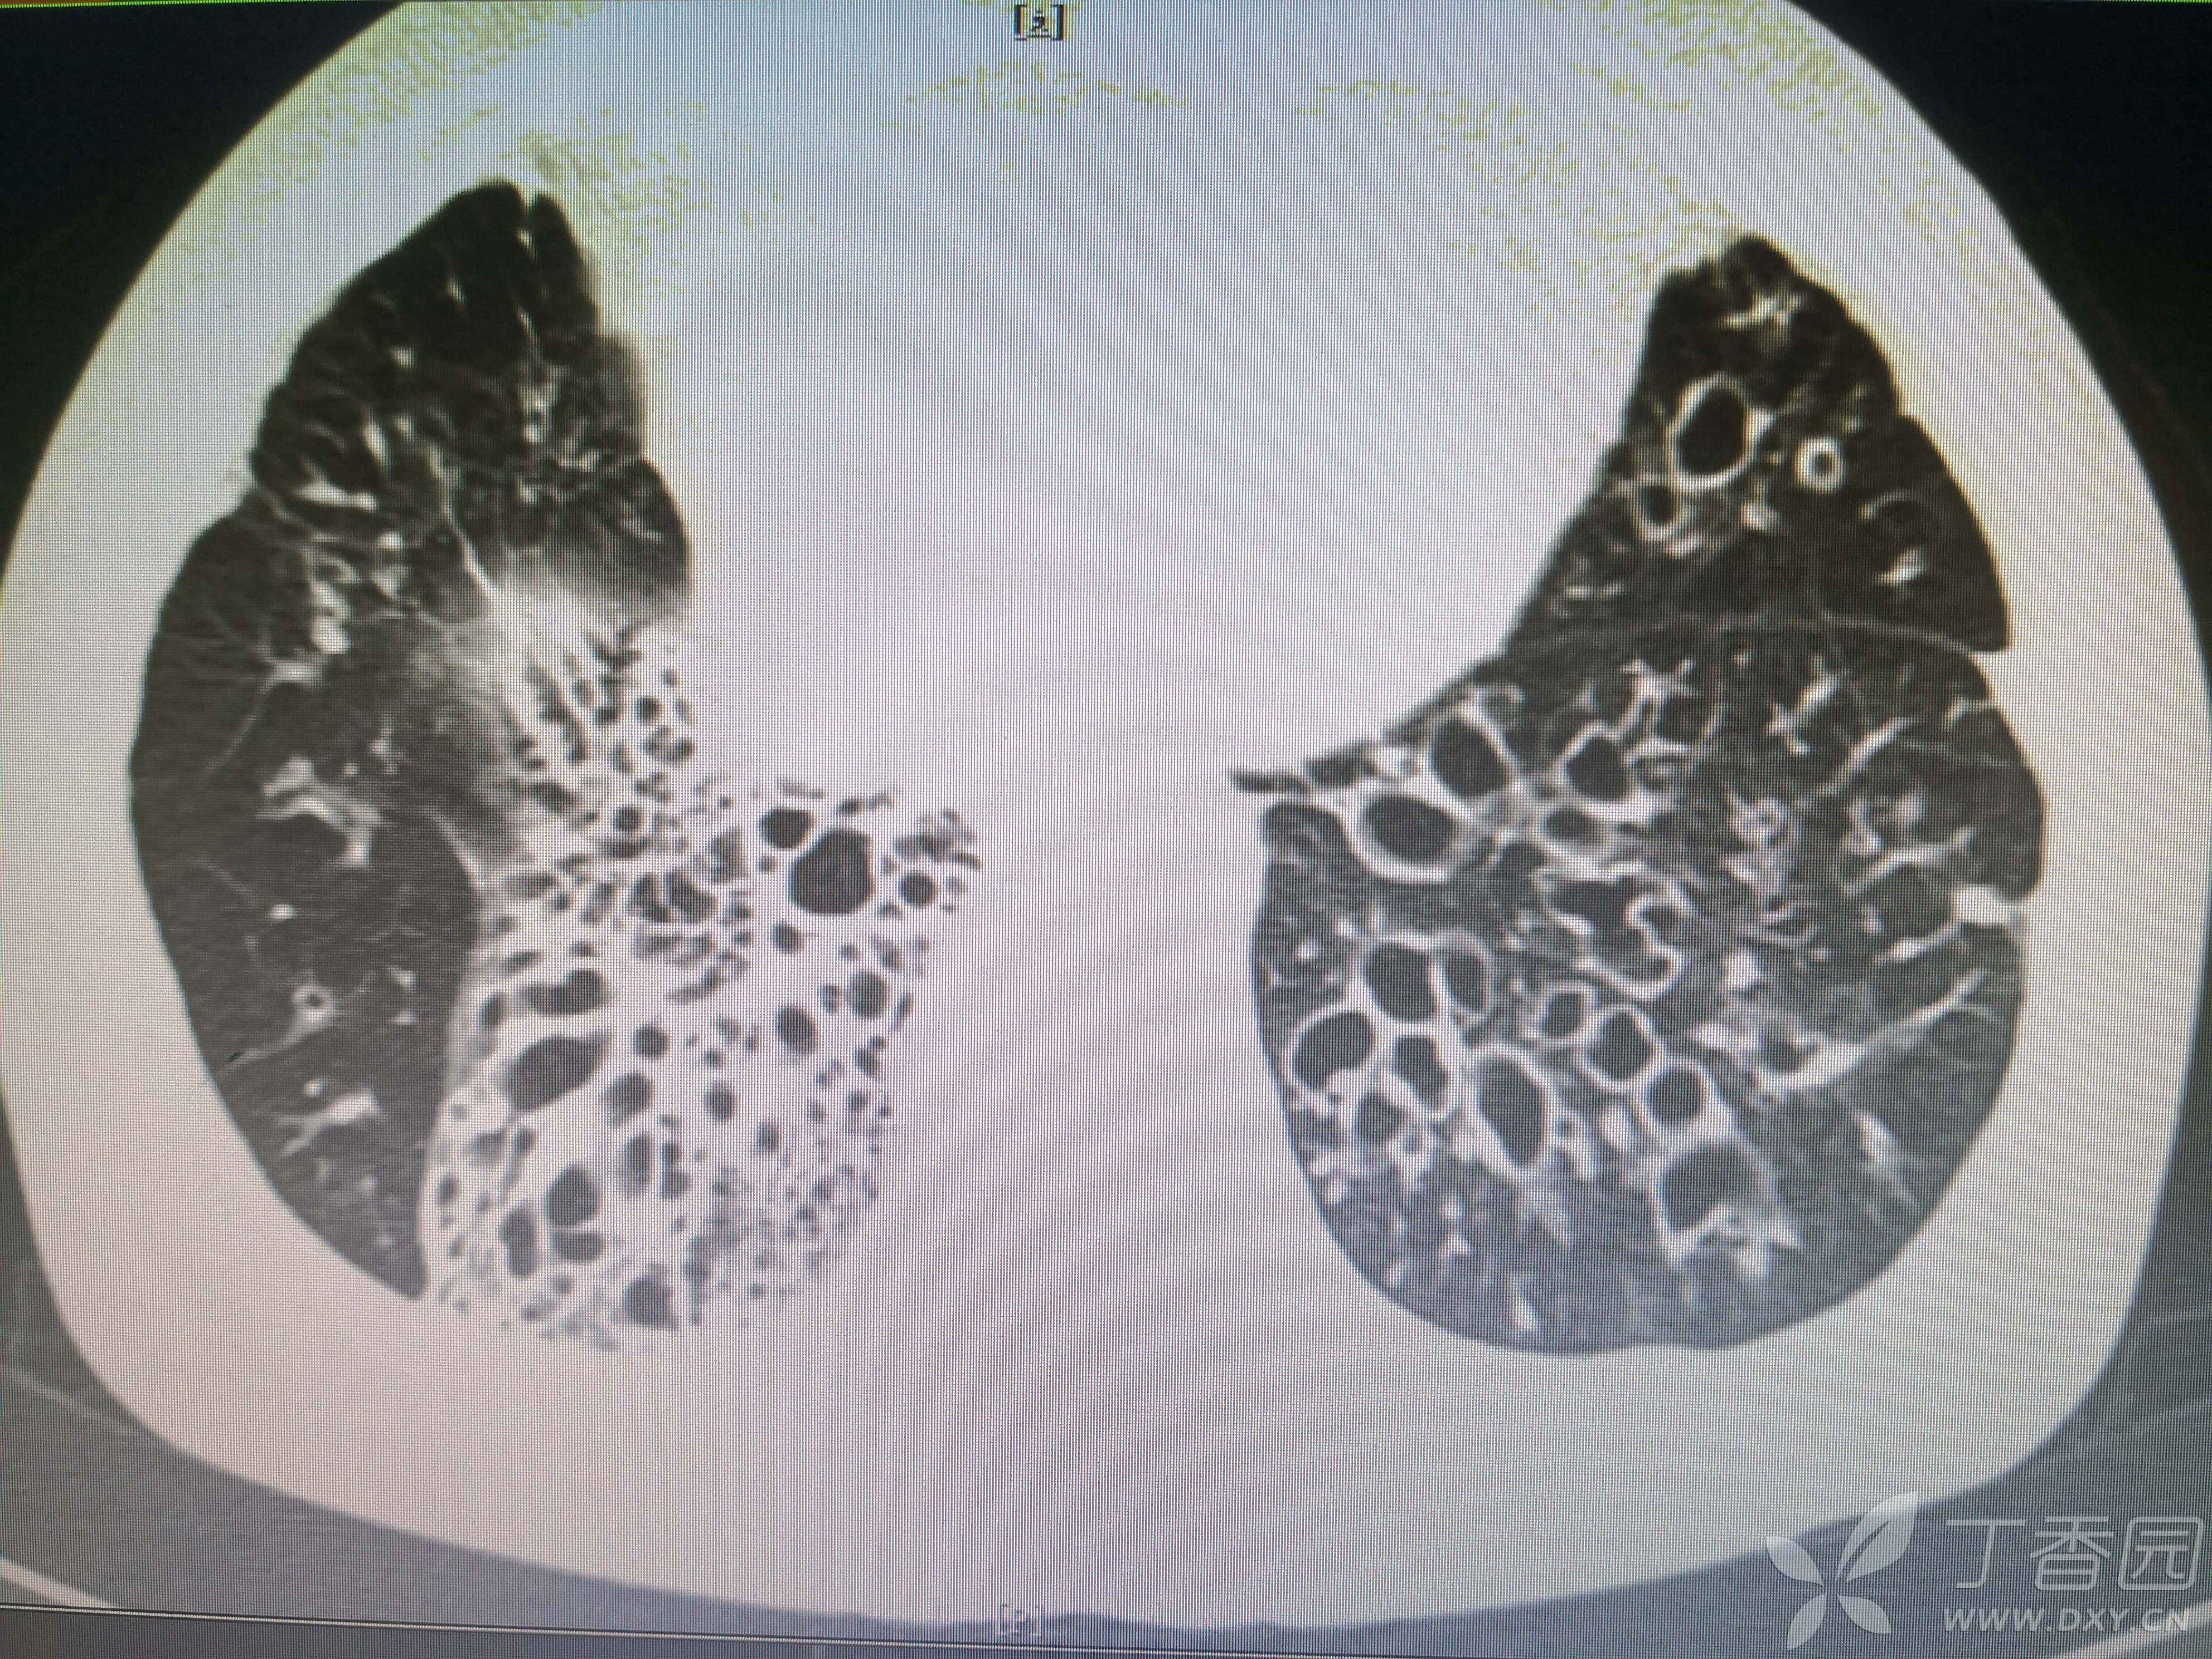

简要病史:反复咳嗽、咳脓痰40余年,气喘10年,加剧2周。

体格检查:SpO2:72%,双中下肺闻及中小湿啰音。

辅助检查:见图

临床诊断:支气管扩张并感染